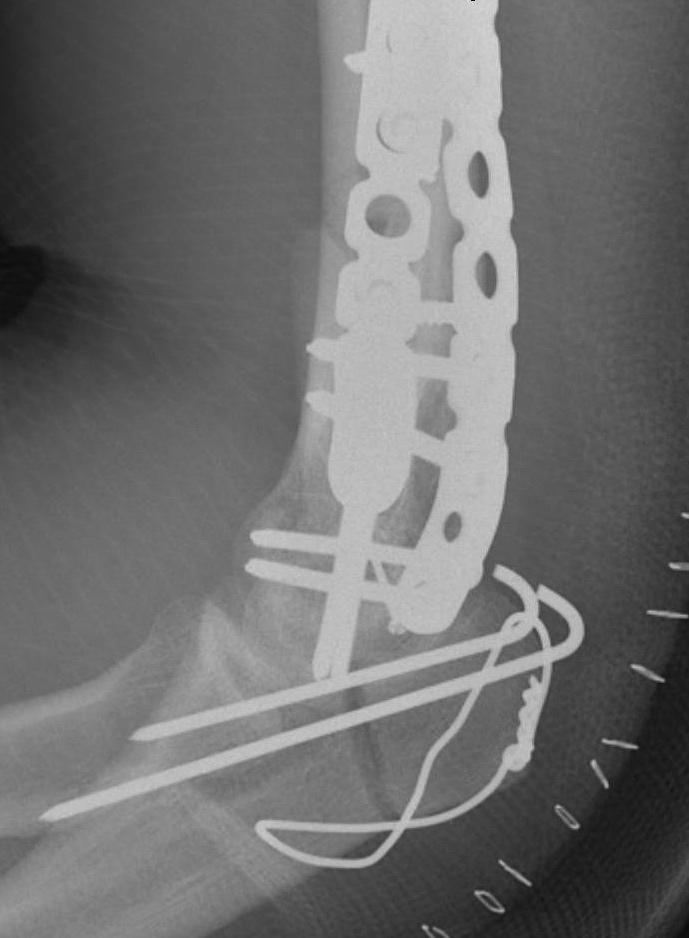

Olecranon Osteotomy

Indication

Complex intra-articular fractures

Technique

Chevron

- distally based V shaped

- through bare area of olecranon / smallest width of greater sigmoid notch

- 3 cm from tip

Fixation

- TBW v plate v intramedullary screw